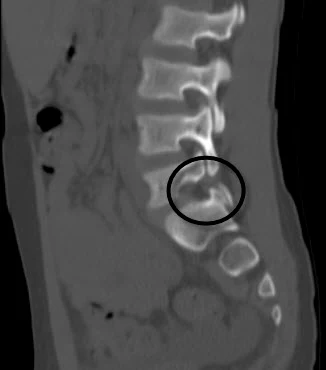

- CT scan (computed tomography) provides a more detailed view of bony structures and is considered the gold standard for visualizing pars interarticularis fractures. CT also has limitations: it is less suitable for early stress fractures that have not yet formed a complete crack, and radiation exposure is much higher than with standard X-rays, which is important to consider, especially in children.

- MRI (magnetic resonance imaging) is particularly useful for early detection of spondylolysis, as it can reveal inflammatory changes and edema in the pars interarticularis before a fracture develops. MRI also allows assessment of morphological changes and neurological complications, such as nerve root compression.